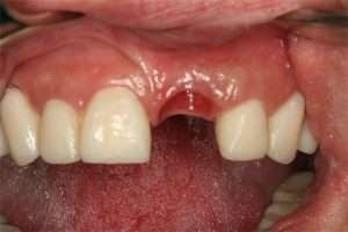

να ανατείλουν και έτσι αποφεύγουμε μελλοντικό εγκλεισμό τους στο οστό της άνω γνάθου. Έγκλειστος κυνόδοντας σε ενήλικα, παρουσία του νεογιλού προγόνου του. Η σημασία της στοματικής υγιεινής και ορθοδοντικής πρόληψης

τον τρόπο αυτό τα βοηθάμε

Ορθοδοντική παρέμβαση στον συγκεκριμένο ενήλικα, μετά από χειρουργική αποκάλυψη του εγκλείστου κυνόδοντα, και μεταφορά του στο οδοντικό τόξο.

Για αποφυγή της παραπάνω διαδικασίας τονίζεται ξανά η σημασία του έγκαιρου ορθοδοντικού ελέγχου στην σχολική ηλικία των παιδιών για τη διάγνωση